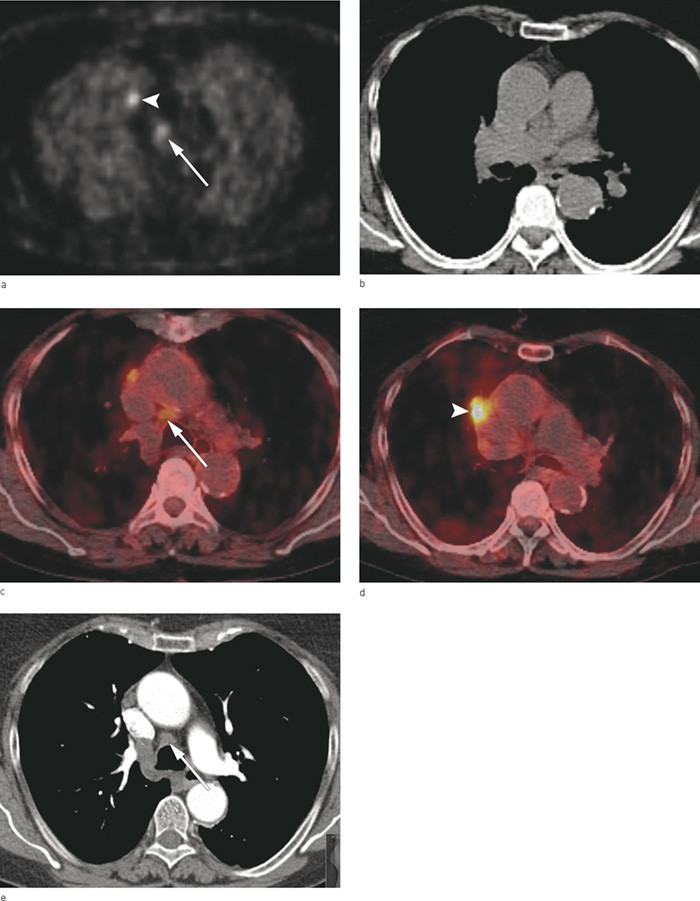

Diagnostisk multidetektor computertomografi (CT) med intravenøst kontrastmiddel er standardundersøkelse for utredning av lungekreft (11). Undersøkelsen gir god informasjon om utbredelse av primærtumor (T-stadium), men har begrensninger når det gjelder å skille maligne og benigne lymfeknuter (N-stadium). I løpet av de siste ti årene er det vist at PET med glukoseanalogen FDG kombinert med CT i samme seanse er den beste avbildningsteknikken for å påvise både spredning til lymfeknuter og ekstratorakale metastaser (12). PET er en funksjonell bildediagnostisk undersøkelse basert på deteksjon av radioaktive isotoper som avgir positroner. FDG er det radiofarmakon (sporstoffet) som oftest benyttes ved PET. Som vanlig glukose tas FDG opp i cellene og gjenspeiler cellenes energibehov. Opptaket er fysiologisk høyt i organer med høy glukosemetabolisme (hjerte, hjerne, lever, nyrer), i inflammatoriske prosesser og i maligne svulster. Visualisering av opptak skjer via en PET-skanner som avbilder og måler fordelingen av det radioaktive stoffet i kroppen (13). I dag brukes integrerte PET-CT-skannere med mulighet for fusjonerte bilder. CT benyttes både for anatomisk lokalisering og for attenuasjonskorreksjon av PET-opptaket for å optimalisere bildene (fig 3a-e).

FDG-PET kombinert med lavdose CT i samme seanse ble utført i en PET-CT-skanner med 64-kanalers multidetektor-CT (Biograph 64, TruePoint PET-CT, Siemens Medical Solutions, Forchheim, Tyskland). Pasientene fastet i seks timer før undersøkelsen. Omtrent en time før skanning ble ca. 370 MBq FDG gitt intravenøst. PET-opptak ble utført under normal respirasjon og i tilslutning til dette ble det gjort lavdose CT fra isse til lår. For pasienter som ikke hadde fått utført multidetektor-CT av god kvalitet i løpet av de siste 4 – 5 ukene på henvisende sykehus ble dette gjort på nytt, enten sammen med PET-undersøkelsen eller på radiologisk seksjon (GE Lightspeed VCT, 64-kanalers CT-maskin) etter intravenøs injeksjon av 100 ml Visipaque 320 mg I/ml (GE Healthcare, Oslo). PET og lavdose-CT ble gransket sammensmeltet og hver for seg, informasjon fra diagnostisk CT gjort ved henvisende sykehus eller ved Rikshospitalet ble også benyttet i vurderingen. PET og lavdose-CT-bildene ble gransket på Leonardo arbeidsstasjon (Siemens Medical Solutions, Forchheim, Tyskland), CT-bildene ble gransket i PACS (picture archiving and communication system fra Sectra Medical Systems, Linköping, Sverige)